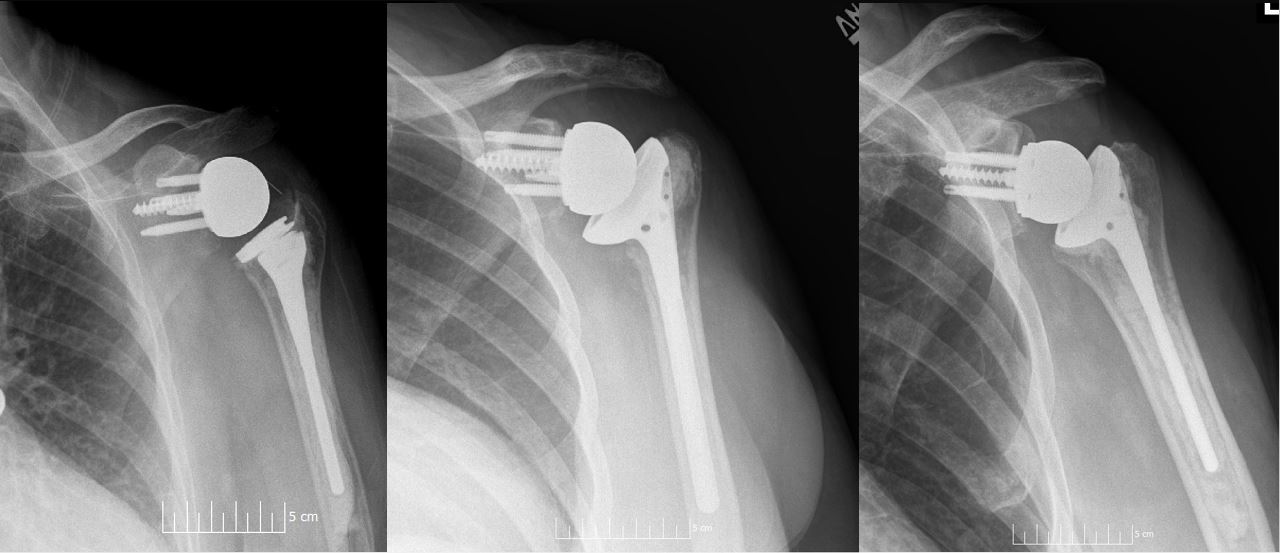

Shoulder phantom with humeral head, glenoid, rotator cuff tendons, labrum, and biceps tendon